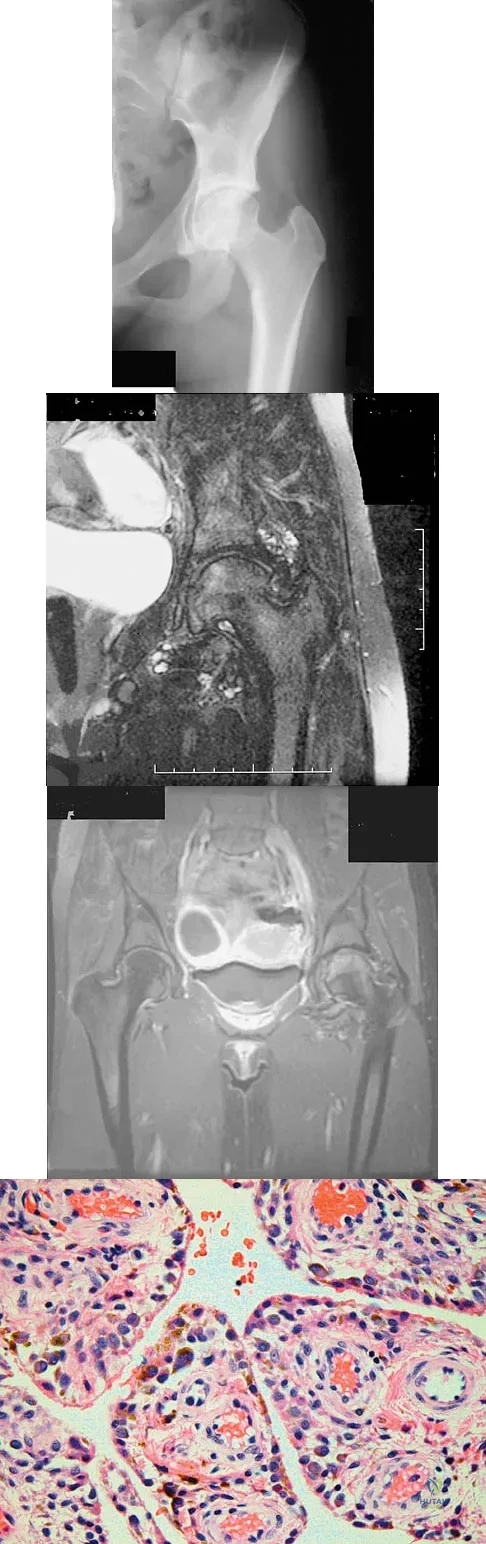

Figures 1a through 1c show the radiograph and MRI scans of a 16-year-old patient who has a painful hip. Examination reveals a significant limp, limited abduction and internal rotation, and severe pain with internal rotation and adduction. A biopsy specimen is shown in Figure 1d. What is the deposited pigment observed in this condition?

Explanation